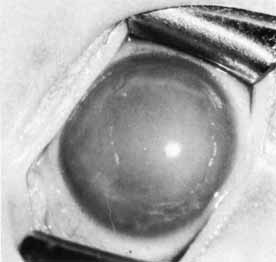

These defects may present as full-thickness holes through the iris with or without sphincter involvement. A more extensive defect with the majority of iris absent is seen in aniridia (Fig. 5).

Fig. 5 Aniridia with cataract. The absence of iris tissue is made more obvious by the lens opacity.

Aniridia is a bilateral congenital anomaly in which the iris is markedly underdeveloped (see Fig. 5). The term aniridia is a misnomer because there is generally a rudimentary iris stump of variable extent visible on examination of the angle.